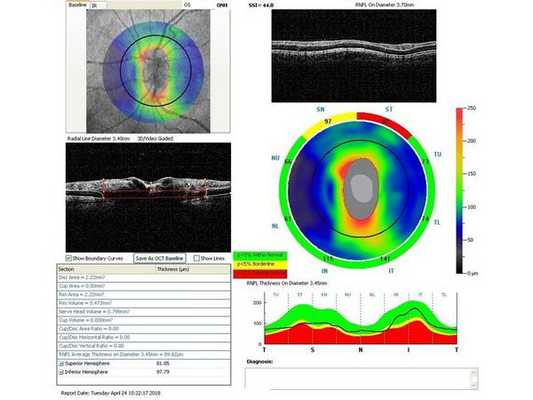

Гониоскопия выявила, что угол передней камеры глаза открыт, профиль радужки плоский, в углу передней камеры по всей окружности визуализируется резидуальная ткань, похожая на пигментированные отростки корня радужки. Она доходит до трабекулярной зоны. Также при первичном осмотре была проведена оптическая когерентная томография (ОКТ)(рис. 1-4).

Через неделю и через месяц после операции пациентка приходила на осмотры для проверки внутриглазного давления, остроты зрения и проведения ОКТ (рис. 5-8). Результаты обследований через месяц после лазерного лечения: ⠀•⠀Острота зрения: ⠀⠀⠀OD: 0,1 sph -2,0 cyl -0,75 ax 85 = 1,0; ⠀⠀⠀OS: 0,1 sph -2,5 cyl -0,75 ax 95 = 1,0. ⠀•⠀Поля зрений - без изменений. ⠀•⠀Тонометрия обоих глаз по Маклакову - 21 мм рт. ст. (без капель). ⠀•⠀Гониоскопическая картина без изменений.